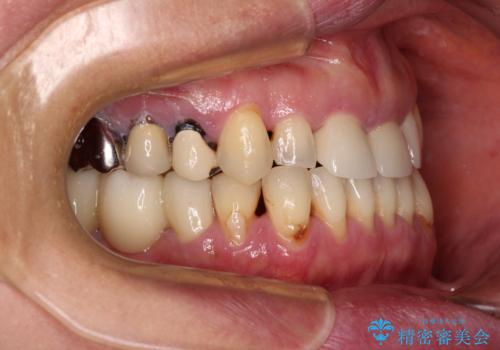

反対咬合や欠損を治療したい インビザライン矯正とオールセラミックブリッジ

- 虫歯治療がうまく進まないとのことで来院された患者様です。

虫歯治療や欠損補綴治療も必要でしたが、前歯が反対咬合であったので、セラミッククラウンやブリッジによる治療と並行して矯正治療を提案しました。

仕事柄海外出張が多いとのことで、虫歯治療後にインビザラインにて矯正治療を行うこととしました。